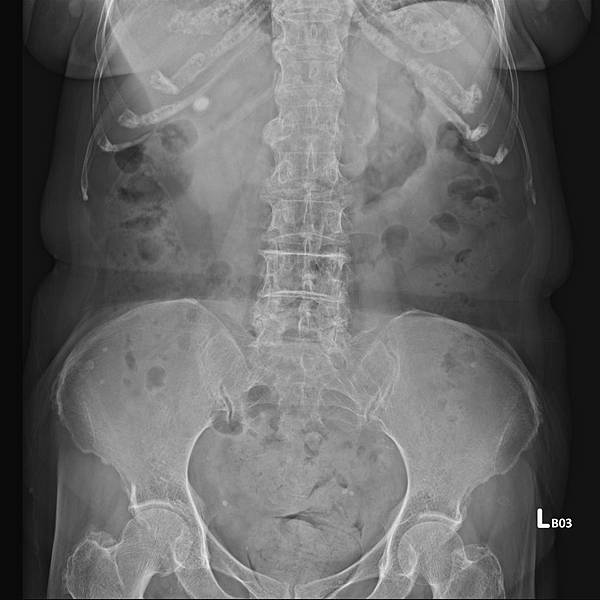

類似的病例很多,下面是上週門診時的胃酸逆流病例,KUB如下:

72歲女性,乙狀結腸(黃箭頭)充滿糞便,但她會告訴你,她每天都有解便。如上圖所示,這樣的病例,病人直腸(藍箭頭)糞便清得很乾淨。